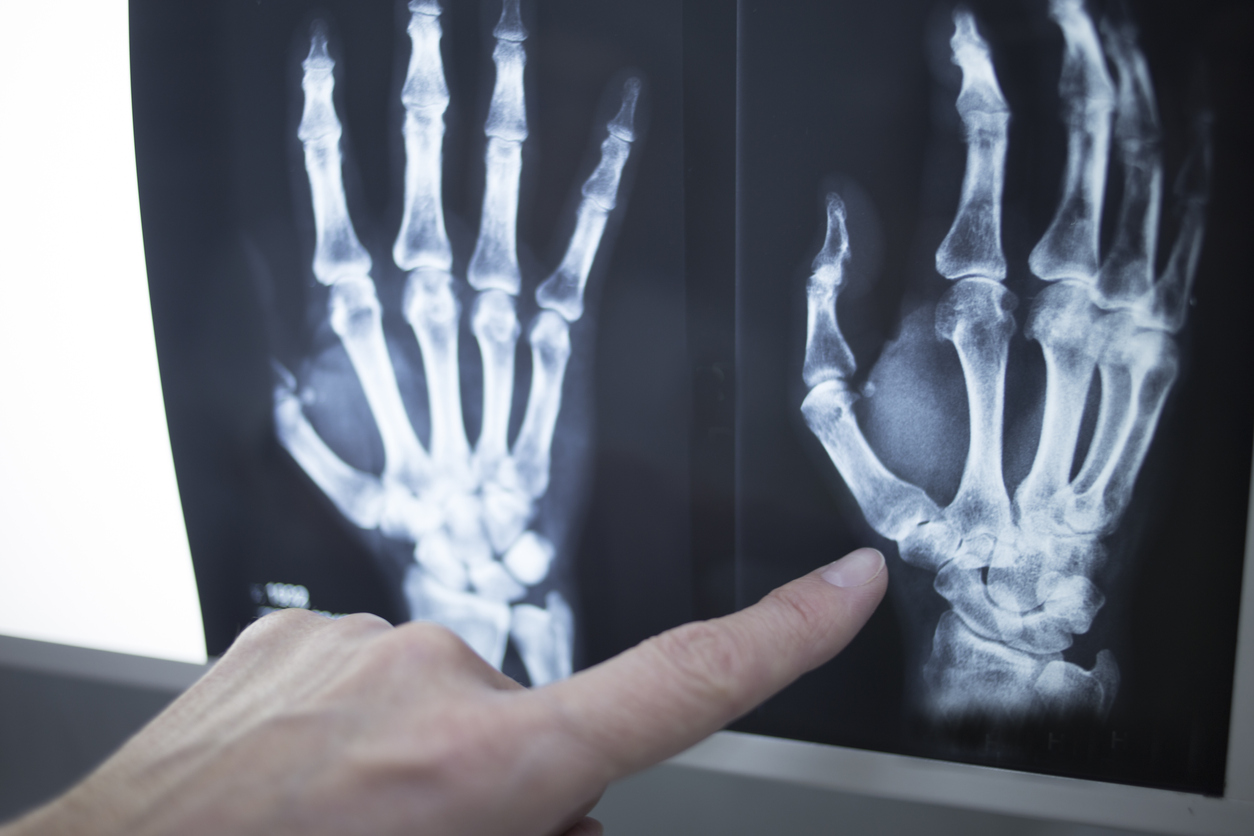

Common Types of Wrist Surgery

Pain in the hand and wrist may have many causes, including injuries and health conditions. Some of these injuries and conditions, when diagnosed early, may not need invasive surgery. However, this isn’t always possible. There are circumstances when wrist surgery is necessary to help bring you relief and restore your mobility. Here are some common…